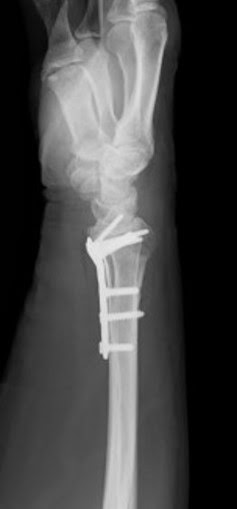

手首の骨折 手術法 医療法人はぁとふる 運動器ケア しまだ病院

· 腕の骨折で子どもが登園禁止に! キプス固定期間のドタバタ生活笑いに変えて乗り切る! (願望) オタク母の育児日記 Vol12|ウーマンエキサイト (1/3) 18年6月6日 10|ウーマンエキサイト コミックエッセイ笑いに変えて乗り切る! (願望) オタク母の育児日記 腕の骨折で子どもが登園禁止に! キプス固定期間のドタバタ生活笑いに変えて乗り切る! (願望手首の骨折 手術法 手首の骨折 手術法 ~最新の手術はギプスがいらない 手術をして早く動かそう~ 手首の骨折(橈骨遠位端骨折:とうこつえんいたんこっせつ)の手術法は進歩しています。従来の手術方法では手術後もギプス固定を行っていました。 · 腕の骨折&手術をされた50歳の上司(事務仕事)退院2~3日後には出勤されてました。 トピ主様は何日間入院されていたのですか? その入院期間